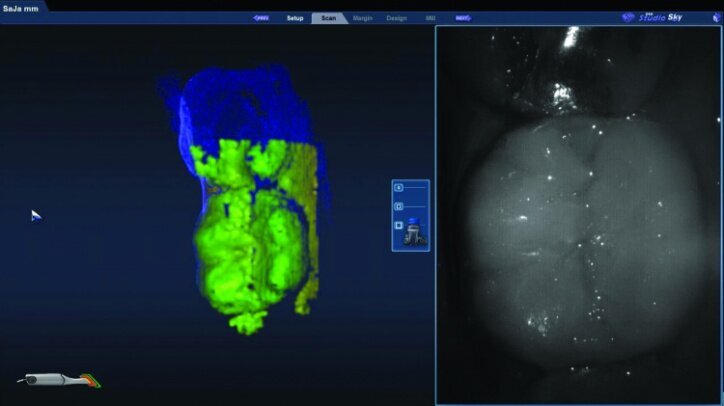

The preparation model was examined in data density view to verify adequate data was obtained during the scanning of the preparations (Fig. 26c).

Any areas lacking adequate data were scanned further until adequate data was obtained. Next, orientation of the preparation model was performed (Fig. 26d). Orientation is for optimal design, not path of insertion. The margins were then traced and viewed in ICE mode, which provides a rendering of the scanned images for a clear view of the margins, teeth and tissues (Figs. 26e, f).

The initial proposals for the restorations were made using Library A and autogenesis, which is morphogenesis of the library tooth with the neighbouring teeth (Figs. 26g–i).